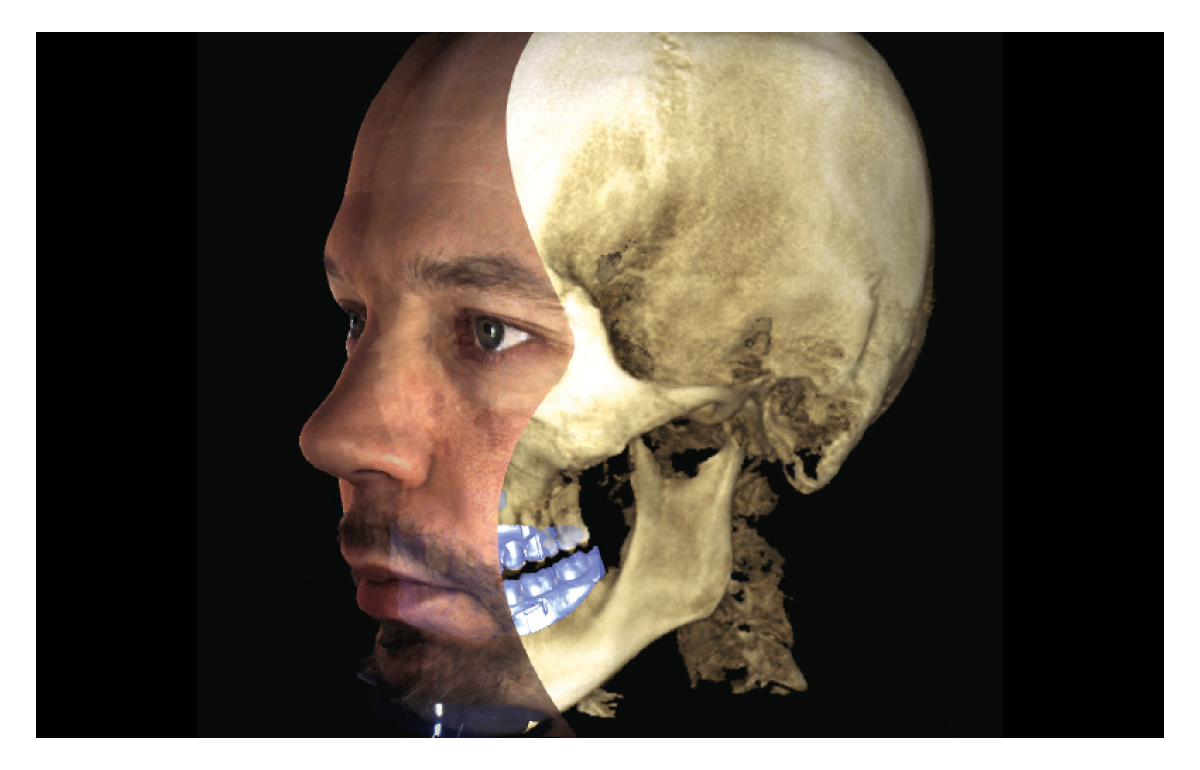

See Beyond the Dentition

Planmeca ProMax 3D is a product family consisting of exceptional all-in-one units. All Planmeca CBCT units support three different types of 3D dental imaging – as well as panoramic, extraoral bitewing and cephalometric imaging. Planmeca is the first company to combine three different types of 3D data within one X-ray unit, ensuring these intelligent machines meet all maxillofacial imaging requirements. The ProMax family brings together a Cone Beam Computed Tomography (CBCT) image, 3D face photo and 3D model scan into one 3D image – using the same advanced software.